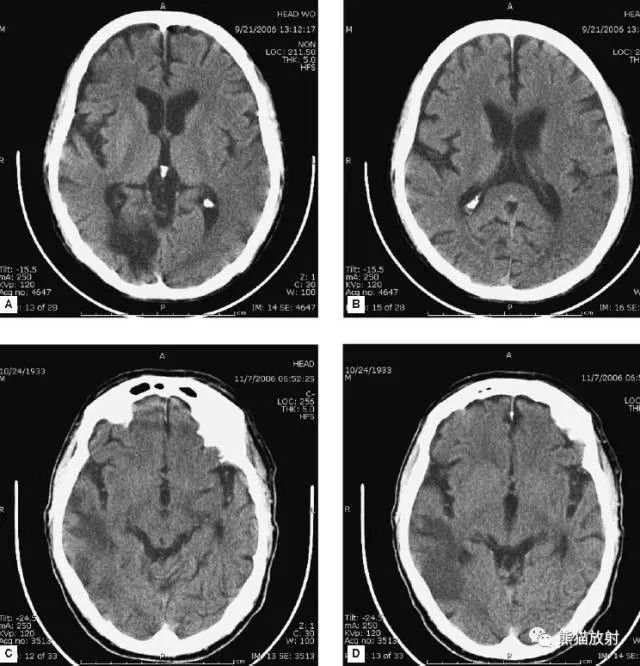

▲动脉瘤破裂导致蛛网膜下腔出血、

脑室积血、非交通性脑积水

与外伤性蛛网膜下腔出血不同,动脉瘤破裂导致的SAH常不累及大脑凸面,而位于基底池附近。脑动脉瘤常位于鞍上池的Willis环血管。

A:四脑室积血;

B:中脑导水管、环池、右侧侧脑室颞角积血,前交通动脉处(动脉瘤好发位置)出血密度较高;

C:三脑室积血;

D-F:侧脑室积血,蛛网膜下腔出血(血液代替了脑脊液)。